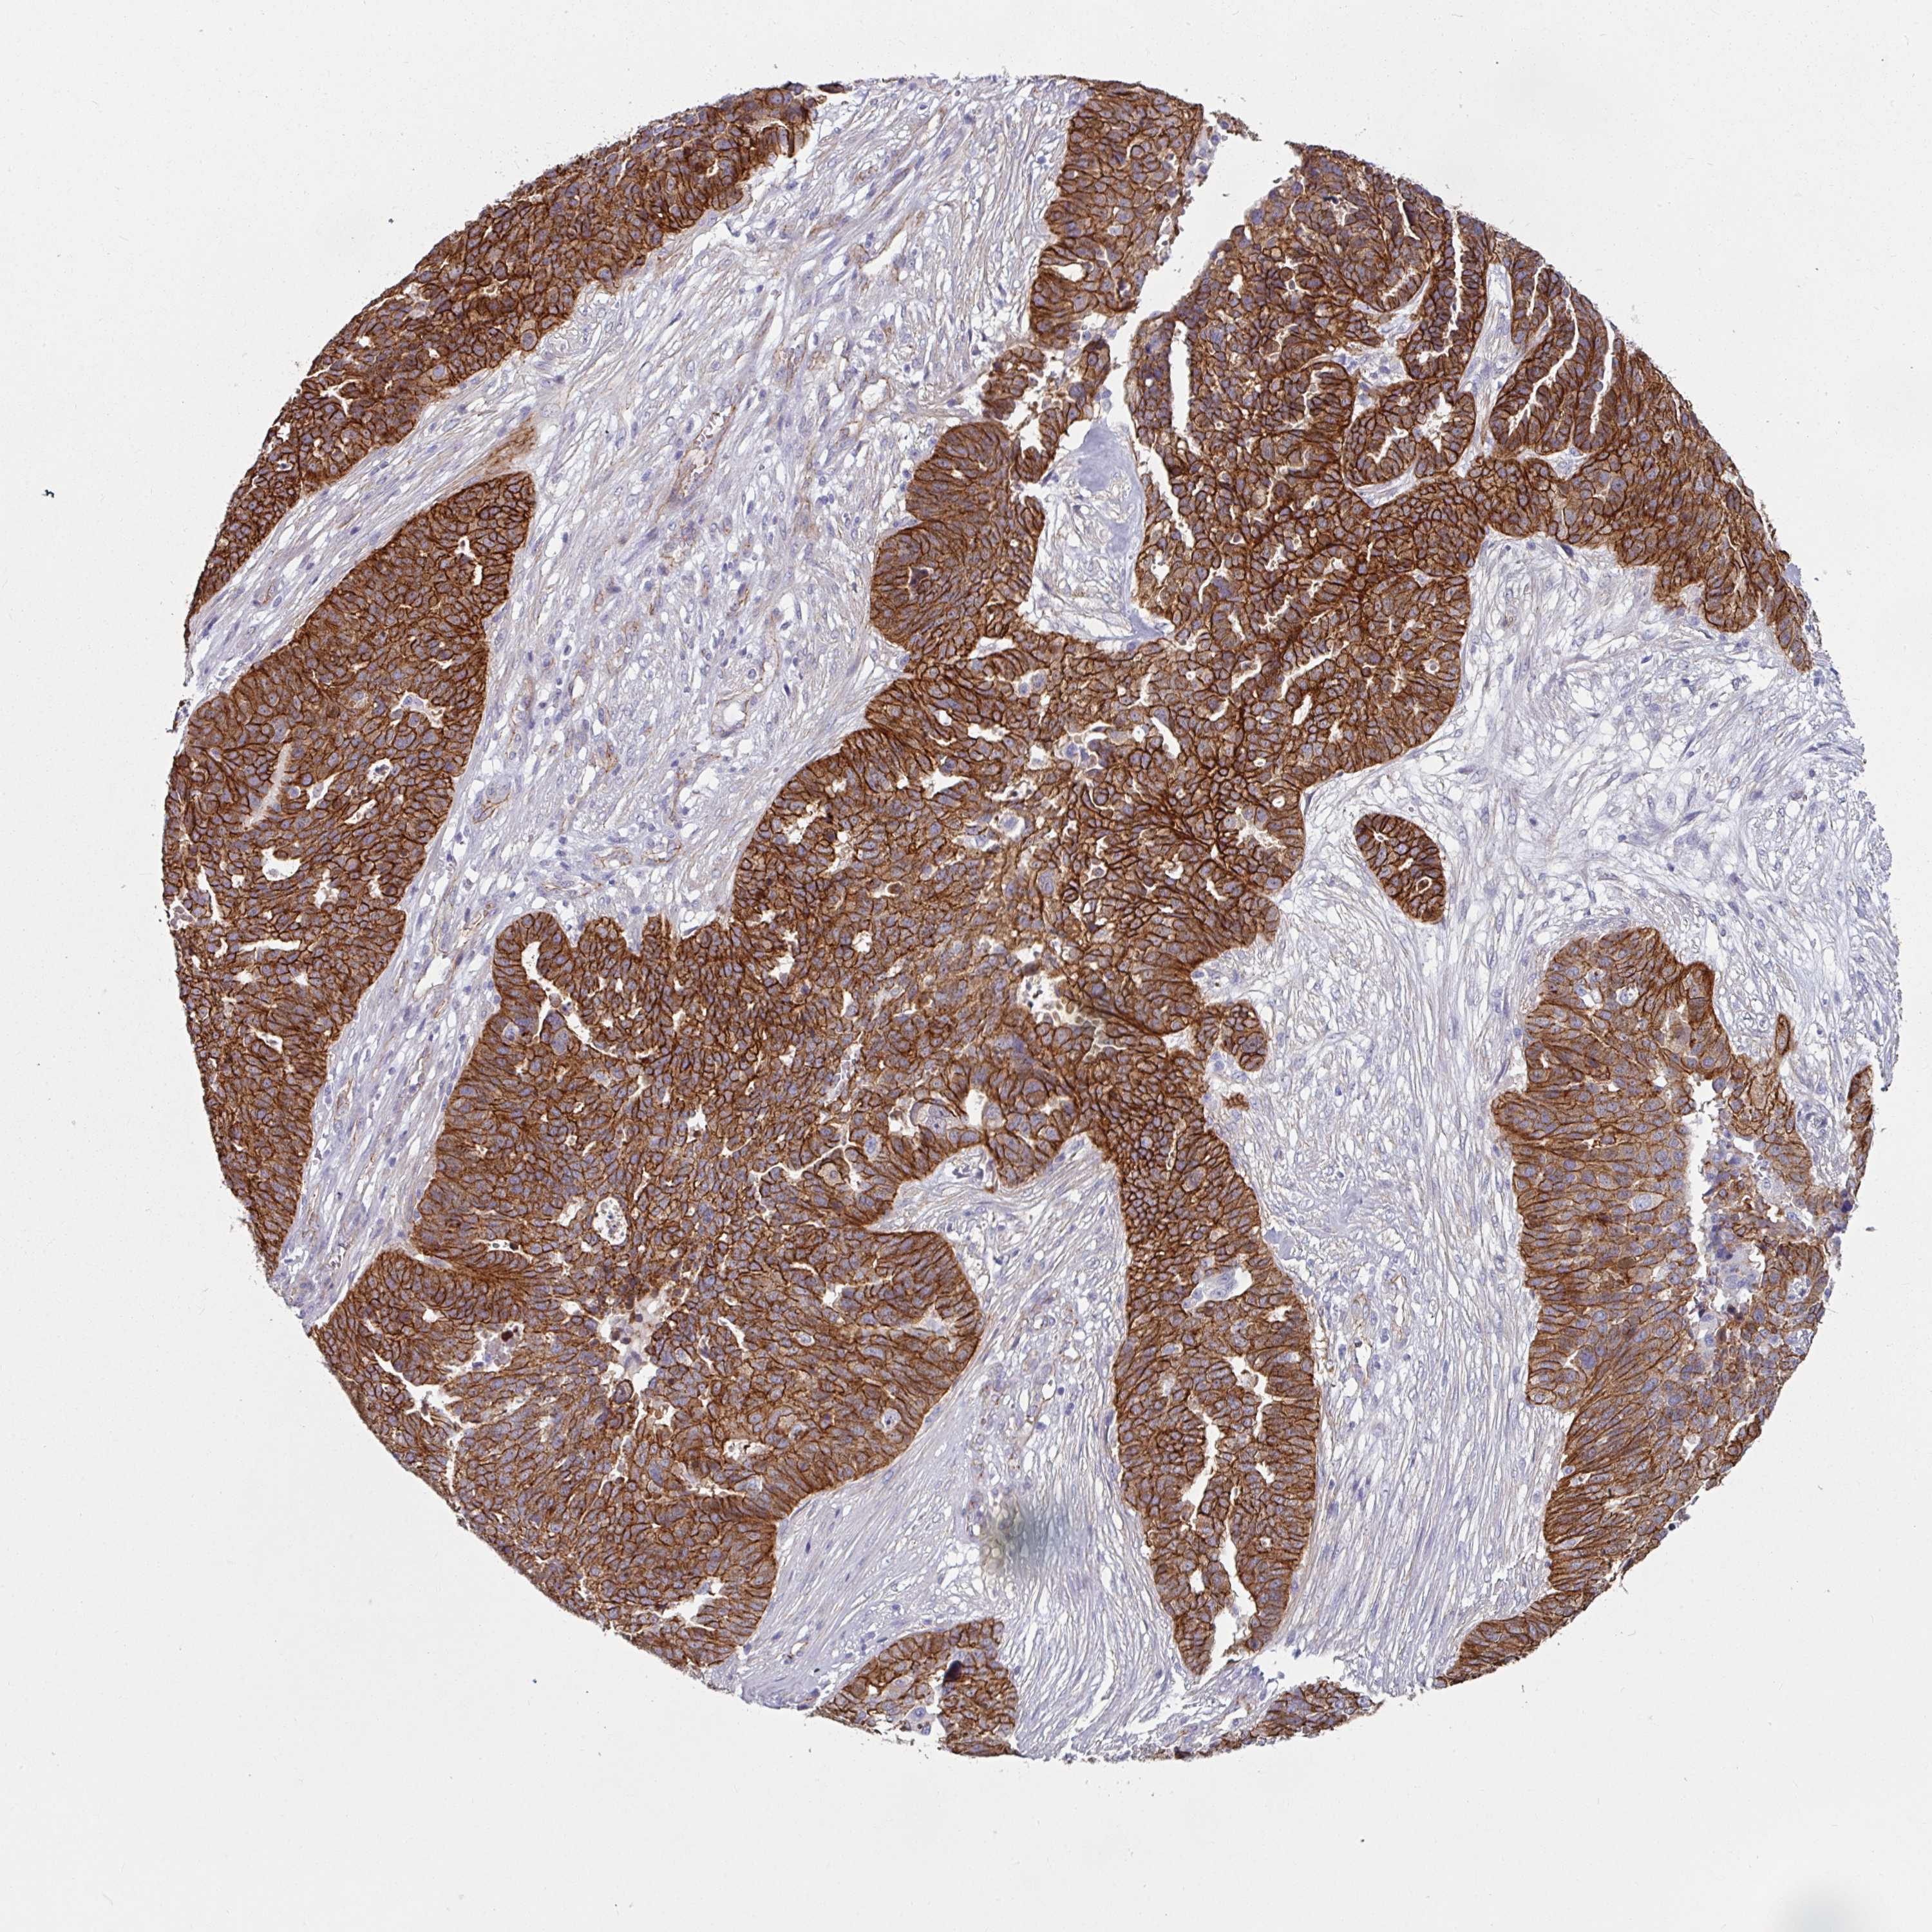

OVARIAN CANCER - Protein expressioni

A mouse-over function shows sample information and annotation data. Click on an image to view it in a full screen mode. Samples can be filtered based on level of antibody staining by selecting one or several of the following categories: high, medium, low and not detected. The assay and annotation is described here.

Note that samples used for immunohistochemistry by the Human Protein Atlas do not correspond to samples in the TCGA dataset.

Antibody stainingi

Antibody staining in the annotated cell types in the current human tissue is reported as not detected, low, medium, or high, based on conventional immunohistochemistry profiling in selected tissues. This score is based on the combination of the staining intensity and fraction of stained cells.

Each image is clickable and will lead to virtual microscopy that enables deeper exploration of all samples and also displays staining intensity scores, fraction scores and subcellular localization as well as patient and tissue information for each sample.

Antibody HPA032047

Antibody CAB002139

Cystadenocarcinoma, serous, NOS

Carcinoma, endometroid

Cystadenocarcinoma, mucinous, NOS

Carcinoma, NOS